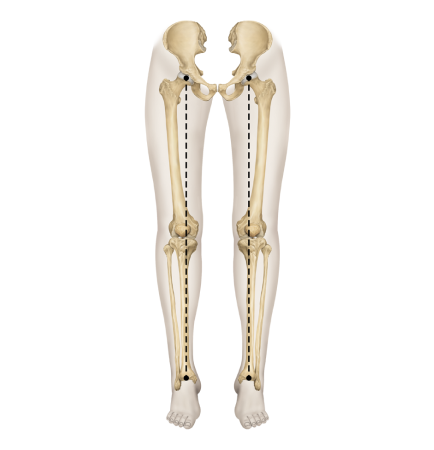

다리의 휜 모양에 따라

▲ O자 다리

▲ X자 다리

▲ 정상 다리

휜다리의 대표적 유형 2가지

O다리

• 무릎이 외측으로 벌어지면서 다리 축이 변형됨

• 체중부하가 다리 안쪽(내측)에 집중되어 내측 관절의 압력증가로

무릎관절의 퇴행성 변화와 통증을 초래

• 허벅지 안쪽 근육이나 엉덩이 근육이 약화되면 무릎 안정성이 떨어져 내반슬이 악화

• 기전

• 방치시

• 악화요인

X다리

• 무릎이 안쪽으로 모이면서 다리 축이 변형됨

• 체중 부하가 다리 바깥쪽에 집중되어 외측 관절의 압력증가로

무릎 통증, 불안정성, 관절 손상을 유발할 수 있음

• 허벅지 바깥쪽 근육이 과도하게 발달하고 안쪽 근육이 약화되면 외반슬이 진행

휜다리는 단순히 무릎 사이 간격이 벌어진 것이 아닙니다.

무릎 위의 대퇴골과 아래의 정강이뼈가 회전하면서 무릎까지 뒤로 빠지기 때문에 다리사이 간격이 넓어지는 겁니다.